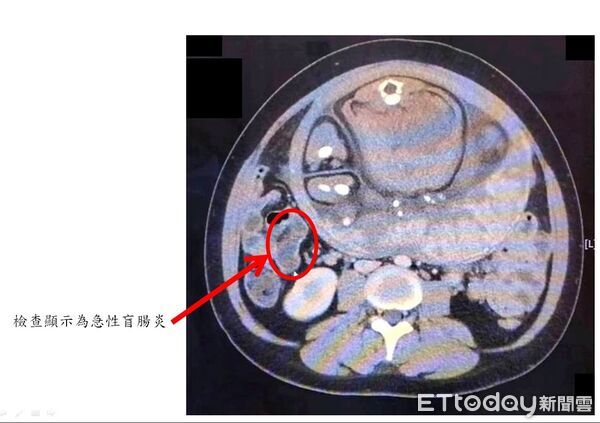

林敬旺說,安排腹部電腦斷層(CT)檢查,並會診一般外科主任劉信誠,經過跨科團隊仔細討論,高度懷疑為急性盲腸炎,且與孕婦及家屬充分溝通解釋後,決定執行緊急剖腹生產併盲腸切除手術。

他表示,手術中發現盲腸已嚴重腫脹化膿,瀕臨破裂邊緣,腹腔內更已有約100毫升的膿樣腹水,情況相當危急。所幸,在妥善保護手術傷口避免污染的情況下,順利接生寶寶,同時完成盲腸切除手術,產婦術後接受抗生素治療,恢復良好、已平安出院。